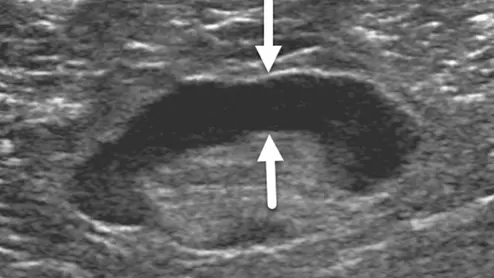

pulsed radiofrequency for sciatica

In PRF procedures, a probe is used to intermittently apply energy directly to the dorsal root ganglia, which is often where pain and neurologic symptoms associated with sciatica originate.